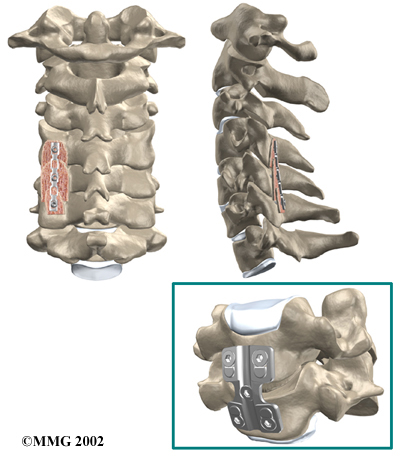

The bone graft needs time to heal in order for the fusion to succeed. This requires the neck to be held still. After cervical fusion surgery, patients usually have to wear a special neck brace for several months. These neck braces are often bulky and restrictive. Recently, surgeons have begun using metal plates and screws (often referred to as instrumentation) to lock the bones in place. The instrumentation is fastened to the vertebrae, where it holds the bones still while the graft heals.

Locking the Bones in Place